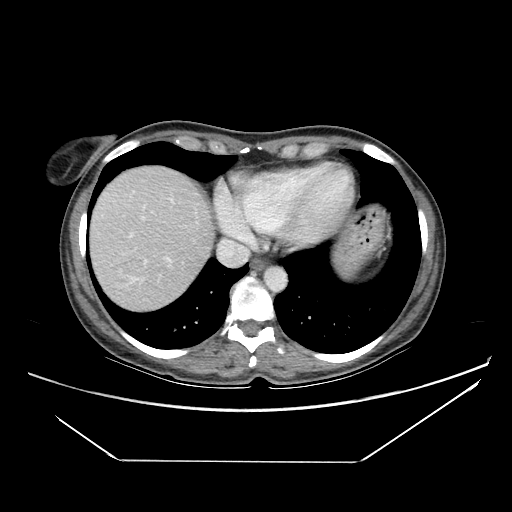

Original NATIVE CT scan (input)

Full window (WL 1023.5, WW 4095 β†’ Low βˆ’1024, High +3071)

Original VENOUS CT scan

Generated VENOUS CT scan (A→B translation)